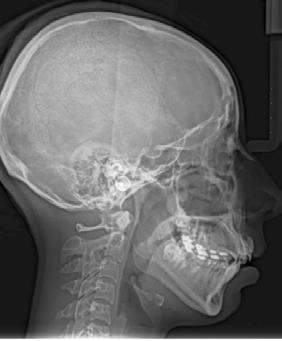

En la ortopantomografía se observó asimetría de las ramas mandibulares, reabsorción radicular severa del diente 21, extrusión de incisivos inferiores y presencia de los dientes 18, 28 y 48 (Figura 2 A). La radiografía lateral de cráneo nos permitió realizar el análisis cefalométrico de Ricketts en el cual se confirmó la clase II esqueletal, el biotipo dolicofacial y la retrusión mandibular (Figura 2 B y C y Tabla 1).

Figura 2. Radiografía ortopantomografía y lateral de cráneo.

En la ortopantomografía se puede apreciar el cierre de la mordida abierta anterior y la preservación de las longitudes radiculares en general (Figura 7A). En la radiografía lateral de cráneo y superposición final se puede observar la mejora general del perfil de la paciente y de sus inclinaciones dentales (Figura 7 B-D) (Tabla 1).